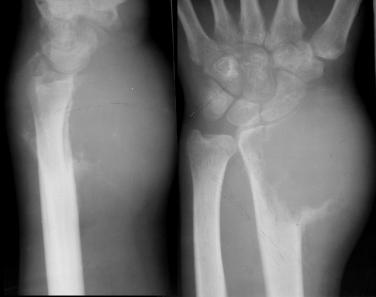

骨巨细胞瘤(GCT)

临床与病理:1、年龄:20-40岁,约65%;2、部位:长管状骨骨端,膝关节附近居多

X线表现:① 多数为偏心性骨破坏 (溶骨型)② 局部骨 膨胀性,骨皮质变薄形成薄层骨壳,无硬化边③ 大小不一的分隔小房呈肥皂泡状, 并见骨嵴。

④ 无骨膜反应,⑤一般不穿破关节软骨

桡骨远端偏侧性膨胀性骨质破坏,中有骨嵴。

20-40岁,股骨下端、胫骨上端、桡骨下端最常见。

偏心性生长,患部肿胀和疼痛,生长快则症状明显;

压痛,乒乓球感;穿破骨皮质:软组织肿块,皮温↑关节活动受限,病理性骨折。

X 线:骨端偏心位膨胀性溶骨性破坏,肥皂泡状,皮质变薄膨大,少有骨膜反应。若骨皮质断裂,骨膜新生骨较明显则提示有恶变可能。